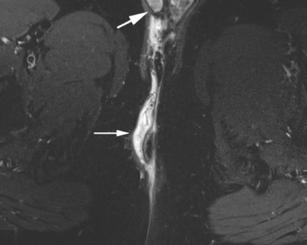

Perianal disease in pediatric Crohn disease: a review of MRI findings

Perianal complications of Crohn disease are a common occurrence in children and can result in significant morbidity when not accurately characterized prior to surgical intervention. MRI is an excellent imaging modality for the evaluation of perianal inflammatory bowel disease – allowing characterization and detailed description of perianal fistulas. MRI has many advantages over other imaging modalities for the pediatric patient. Radiologists will benefit from a sophisticated understanding of perianal anatomy, the classification of perianal fistulas, the advantages MRI offers in characterization of perianal fistulas as well as the common and incidental findings that are important in the MRI evaluation of perianal inflammatory bowel disease in children. Perianal fistulas are found at a high rate in pediatric referrals and are more commonly found in male patients.